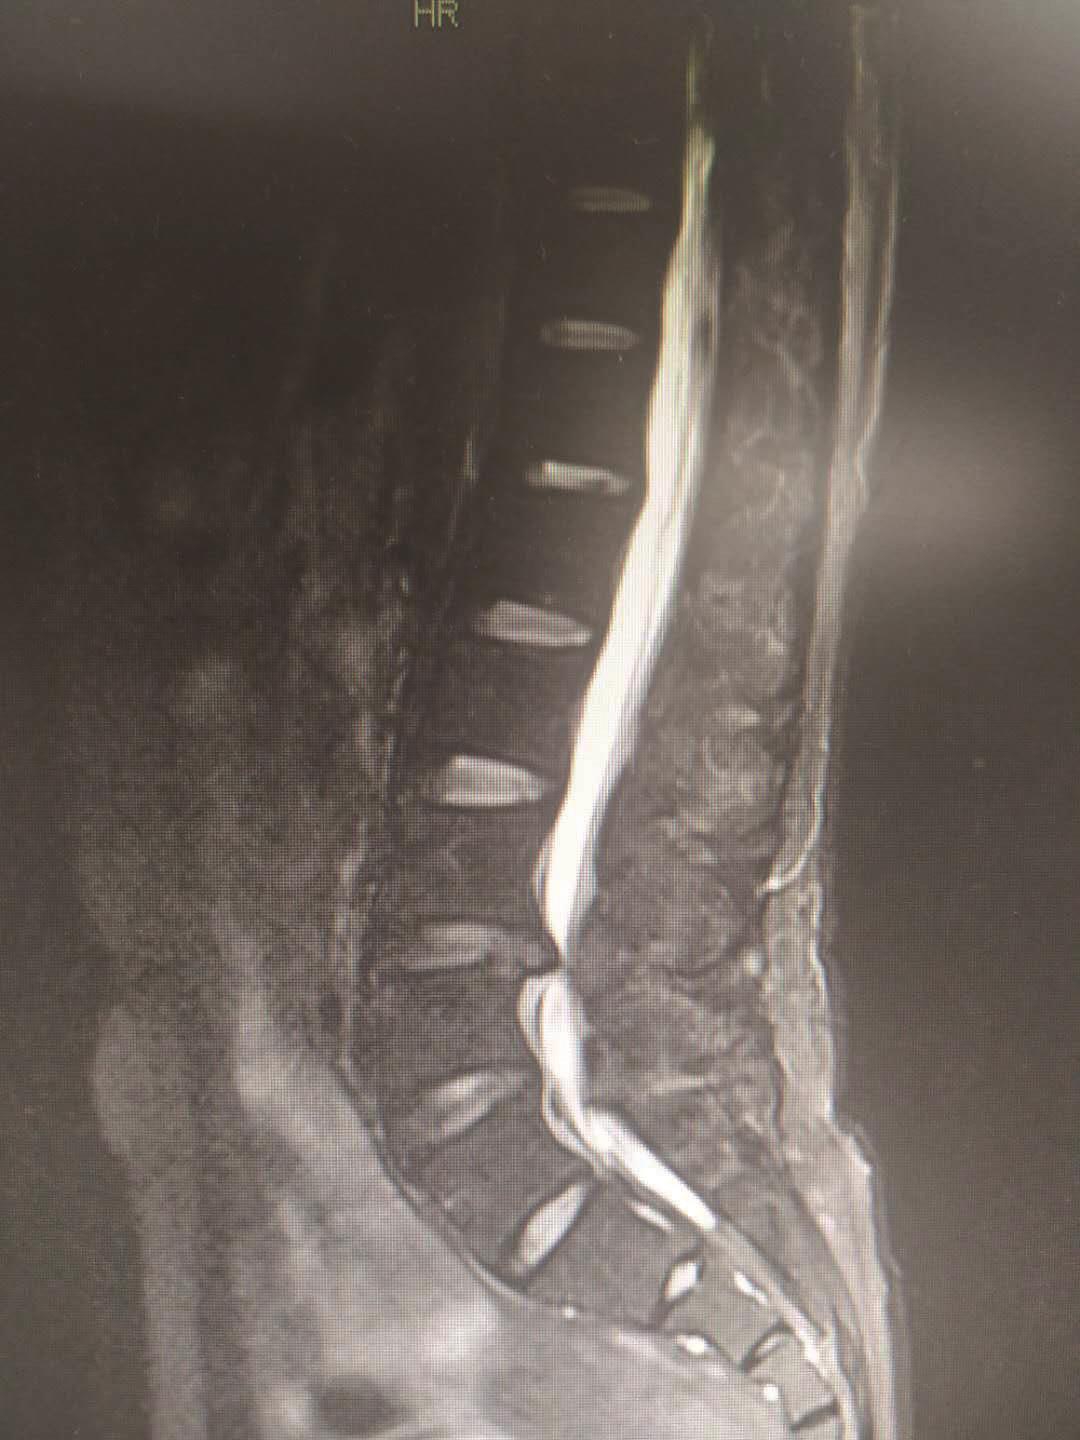

磁共振检查能够清楚地了解椎间盘退行性变、髓核突出的情况。